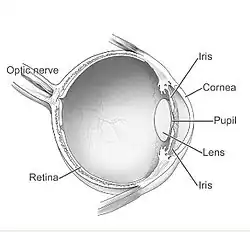

Corneal neovascularization (CNV) is the in-growth of new blood vessels from the pericorneal plexus into avascular corneal tissue as a result of oxygen deprivation.[1] Maintaining avascularity of the corneal stroma is an important aspect of healthy corneal physiology as it is required for corneal transparency and optimal vision. A decrease in corneal transparency causes visual acuity deterioration. Corneal tissue is avascular in nature and the presence of vascularization, which can be deep or superficial, is always pathologically related.[2]